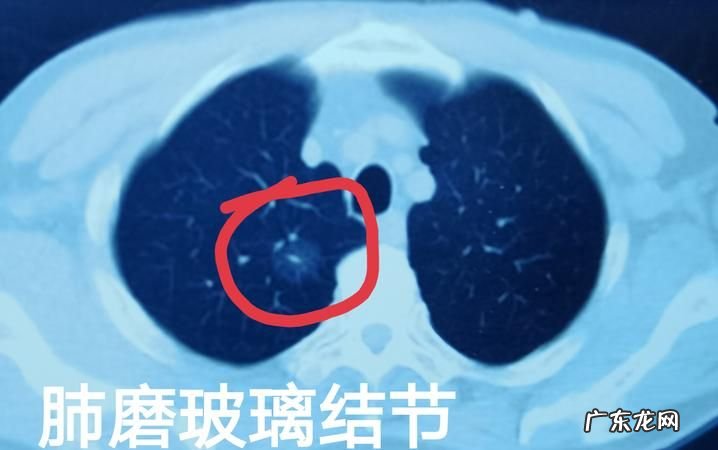

3、非实性结节常为癌前或者是癌性病变,随访时间应该延长,并且根据恶性风险选择相应的处理措施 。